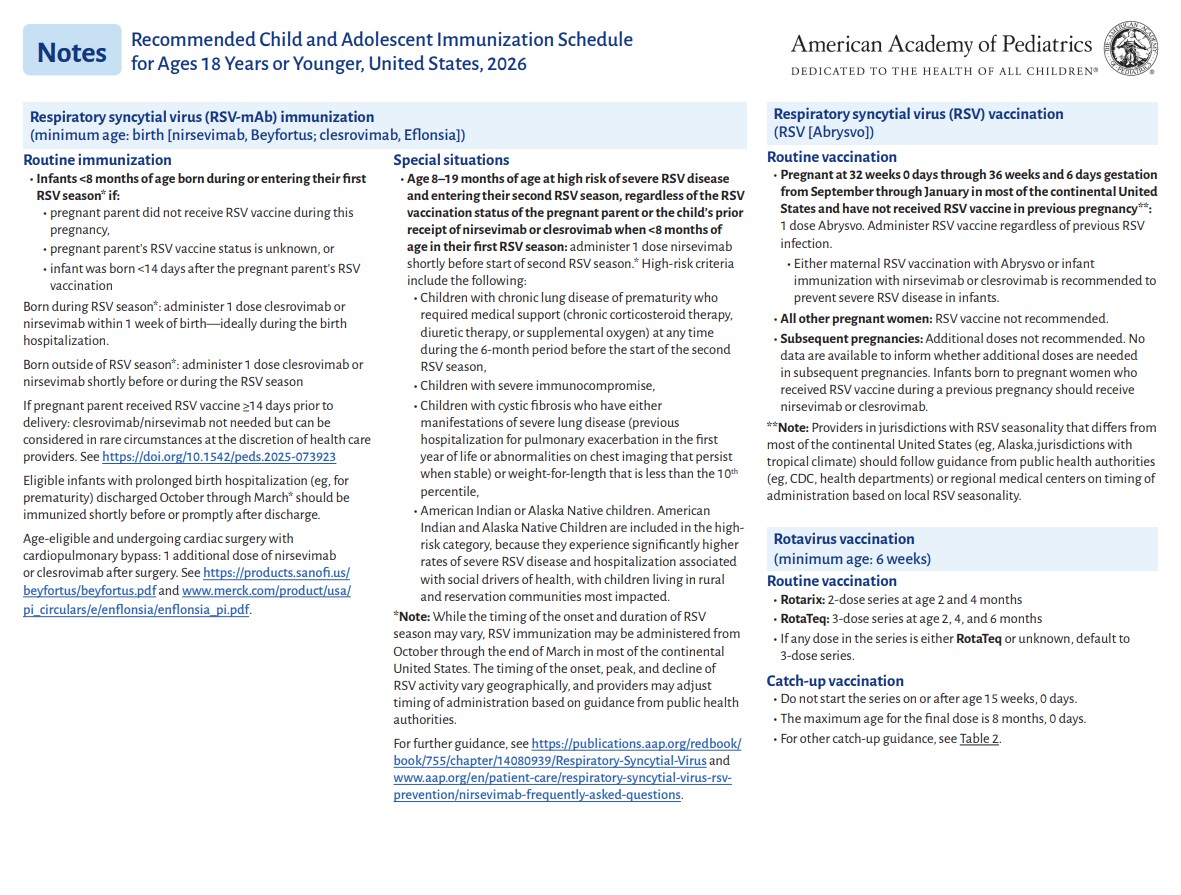

p 1

p 2